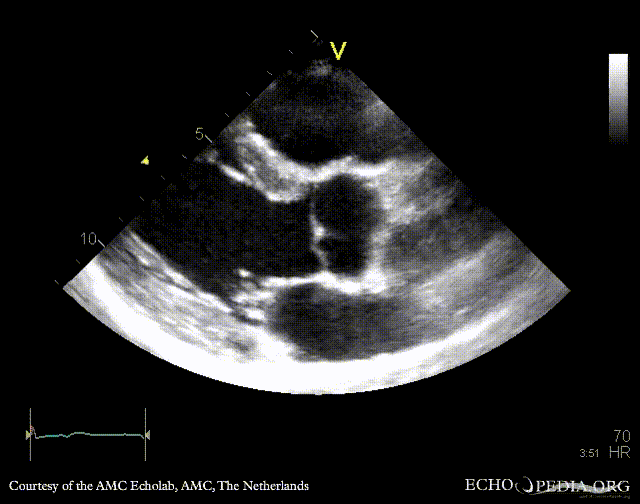

PLAX: bicuspid aortic valve, doming of aortic valve PLAX: Color Doppler, mild aortic regurgitation